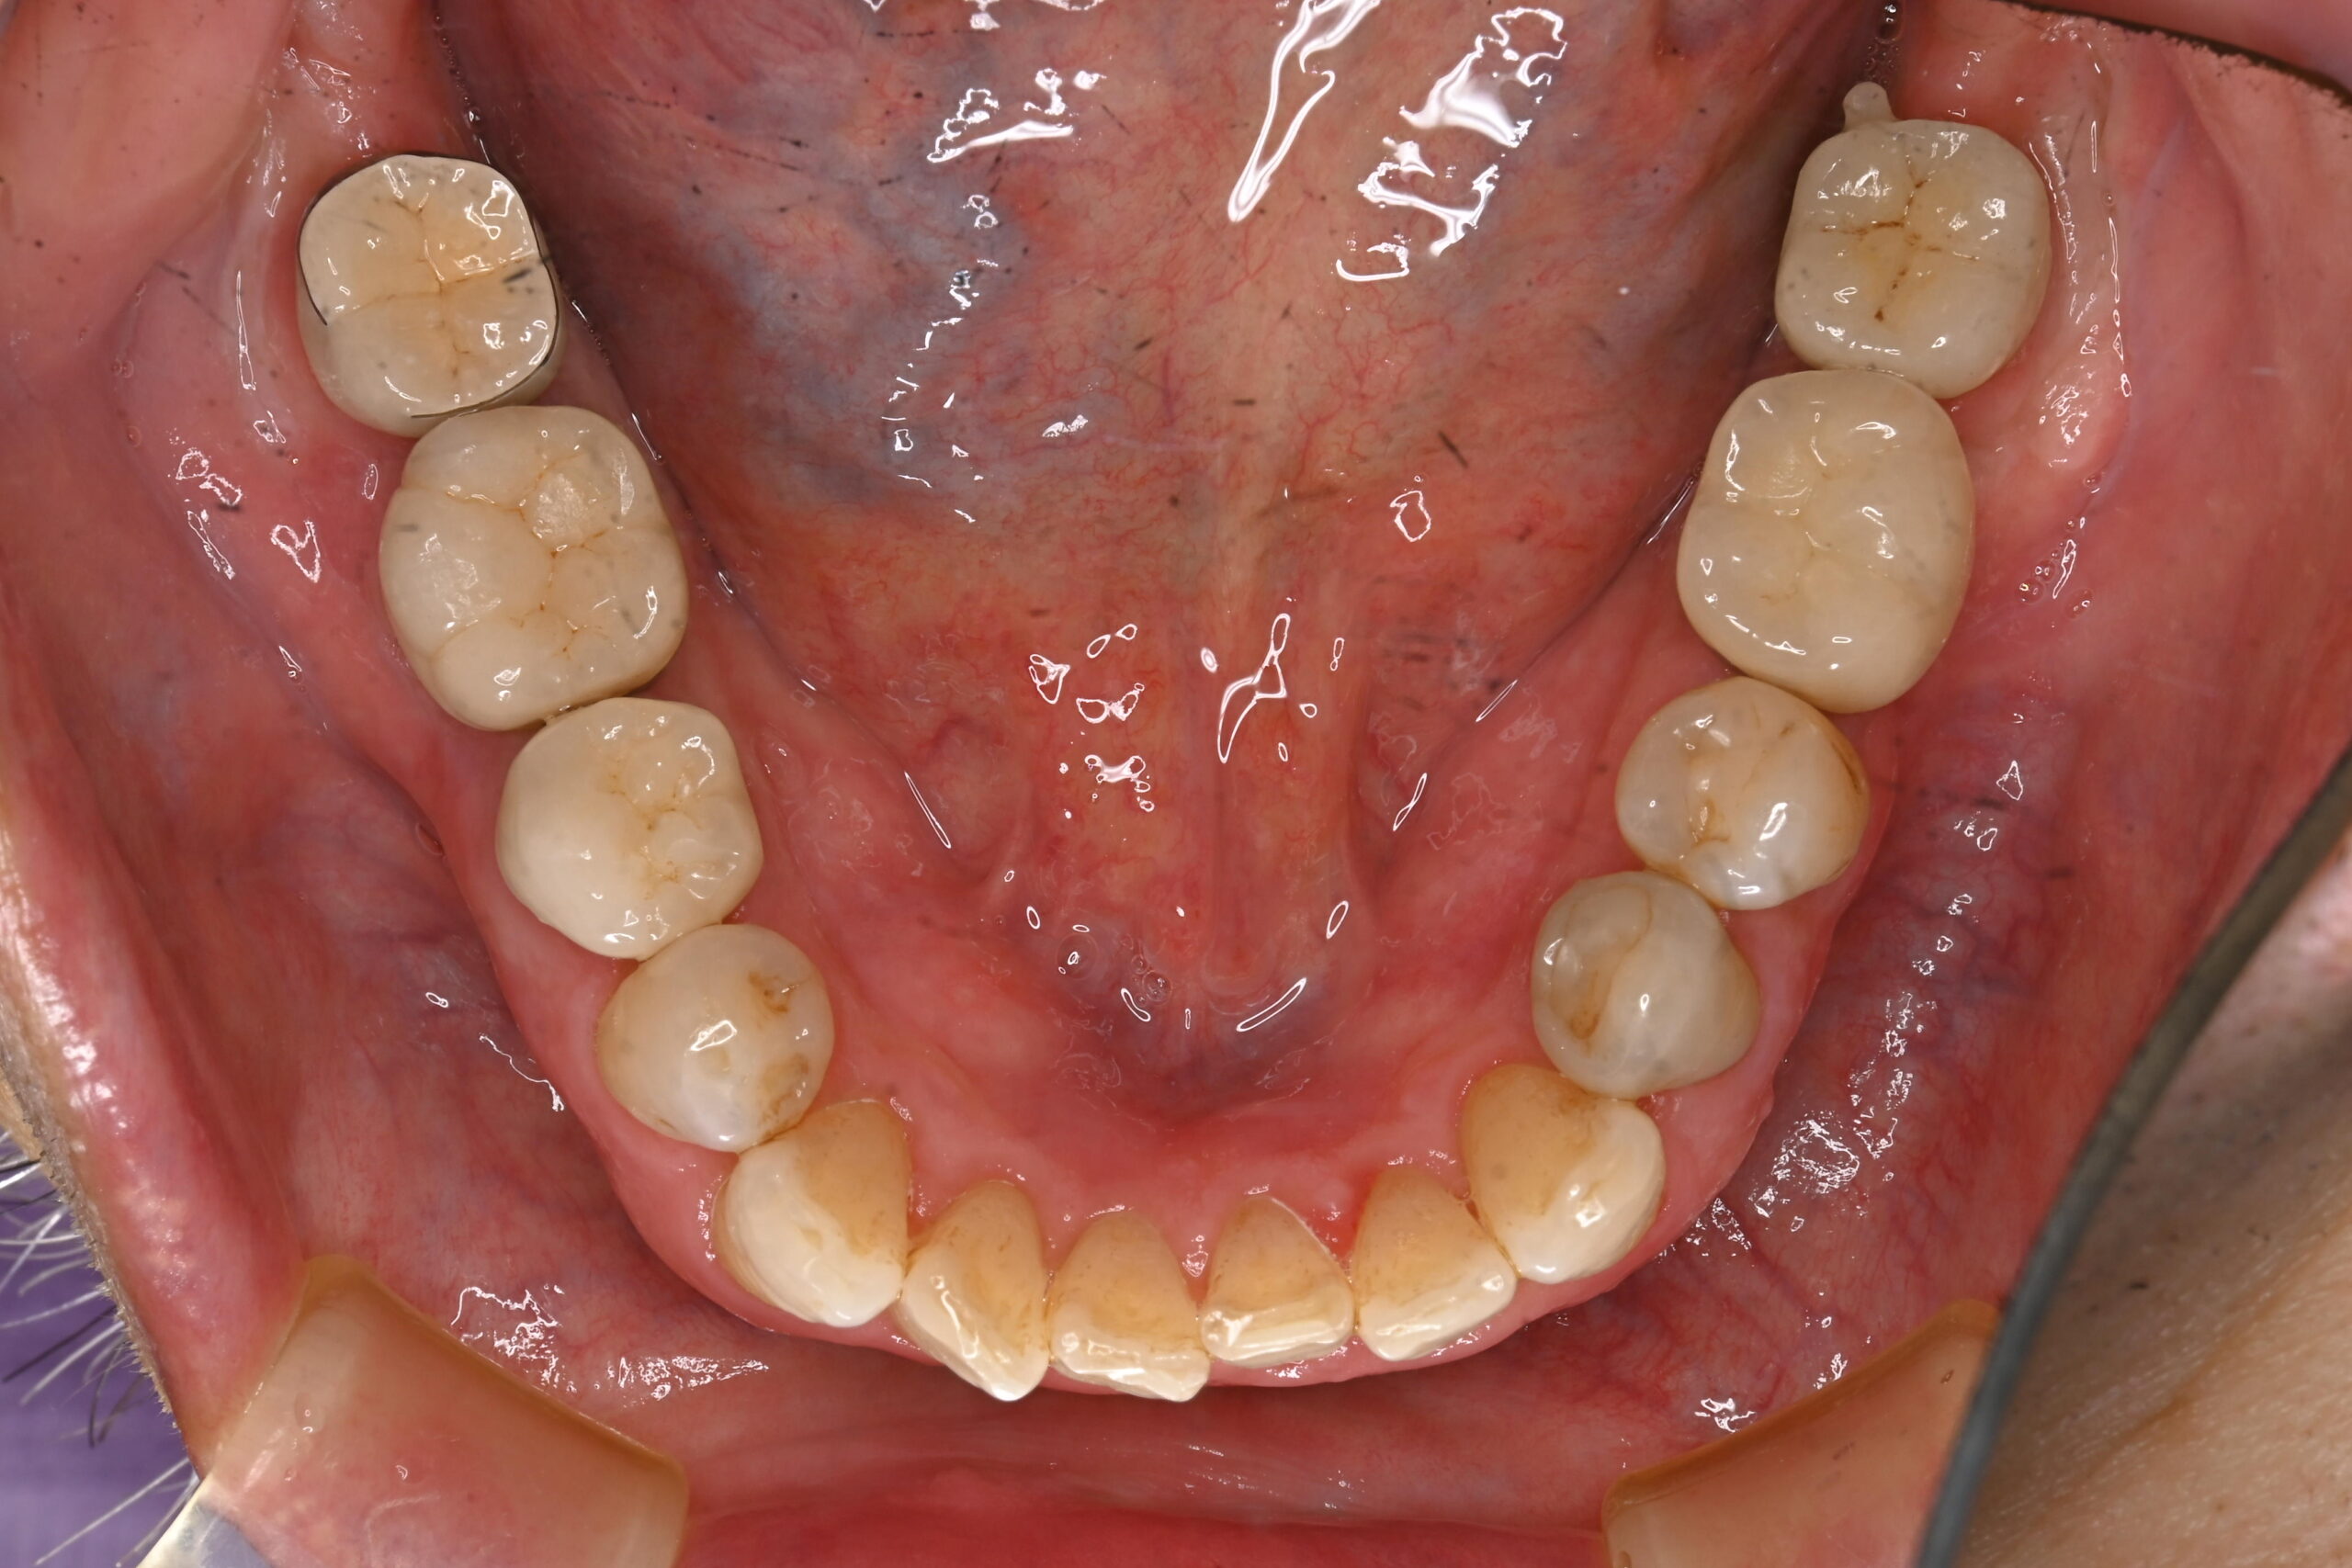

奥歯が欠けた|下顎左右6番の抜歯に伴うインプラント治療

症例写真 before

左右の下の奥歯が欠けたという主訴で来院されました。

診断の結果、下顎左右6番の根尖性歯周炎と2次虫歯が認められました。

どちらの歯も状態が悪く保存的処置が望めませんでした。患者さんとの相談の結果、抜歯しインプラントを埋入することになりました。

まず右下6番の抜歯、インプラント埋入手術、上部構造の装着を行い、次いで左下6番の治療を右下同様に進めました。

上部構造装着後10年以上経過しますが、定期的なメインテナンスと患者さんの日々のケアの甲斐あって、現在まで良好な経過をたどっています。